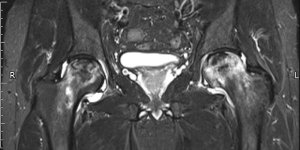

Hip Osteonecrosis | Cases

Published on Jan 20, 2021

59 ♂ B/L groin pain. 10/10 VAS Initially started on the left side like lateral hip pain. Had 2 steroid injections for lateral hip pain. Uses walking stick. Painful with weight bearing, getting in / out of car. No spinal symptoms. Recent X-ray NAD Exam Antalgic gait Pain deep in groin Hip flexion limited to 90° B/L Minimal internal and external [...] Read more